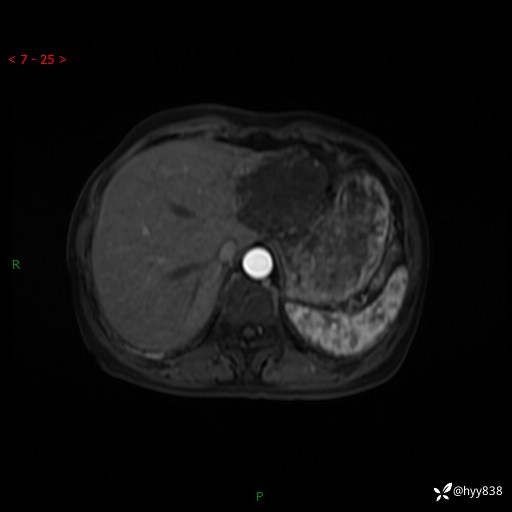

辅助检查:MRI

肝脏MRI平扫(同反相位)

T2WIfs+DWI

增强(动脉期+静脉期+延迟期)